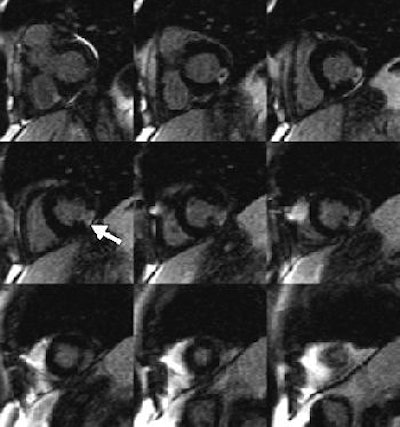

![]() |

| Representative baseline short-axis MOLLI T1 maps from all three studies in 27-year-old woman (volunteer 5). The spatial resolution (pixel size, 1.6 x 2.3 mm) is high enough to enable detection of left ventricular papillary muscles and trabeculations. Each of these maps was based on 11 steady-state free precession source MR images (3.90/1.95; flip angle, 50°; matrix, 240 x 151; section thickness, 8 mm). Figure 1. Messroghli DR , Plein, S, Higgins, DM, et al, "Human Myocardium: Single-Breath-hold MR T1 Mapping with High Spatial Resolution -- Reproducibility Study" (Radiology 2006; 238:1004-1012). |